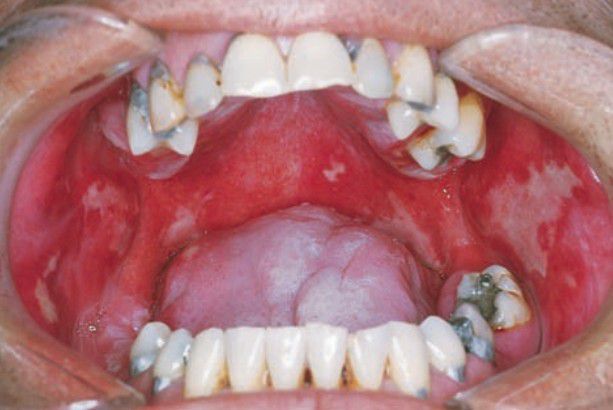

Radiation mucositis

This is a side effect of radiation in case of head and neck cancer